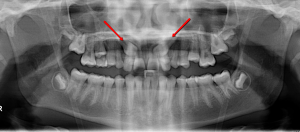

Before

Impacted Teeth Exposed

Usually the impacted tooth is exposed over the course of a few months and brought into the correct position of the mouth. Correction of impacted teeth may involve a minor surgical procedure performed by an oral surgeon working closely with our practice. This will allow us to then guide eruption of the impacted tooth into proper position.